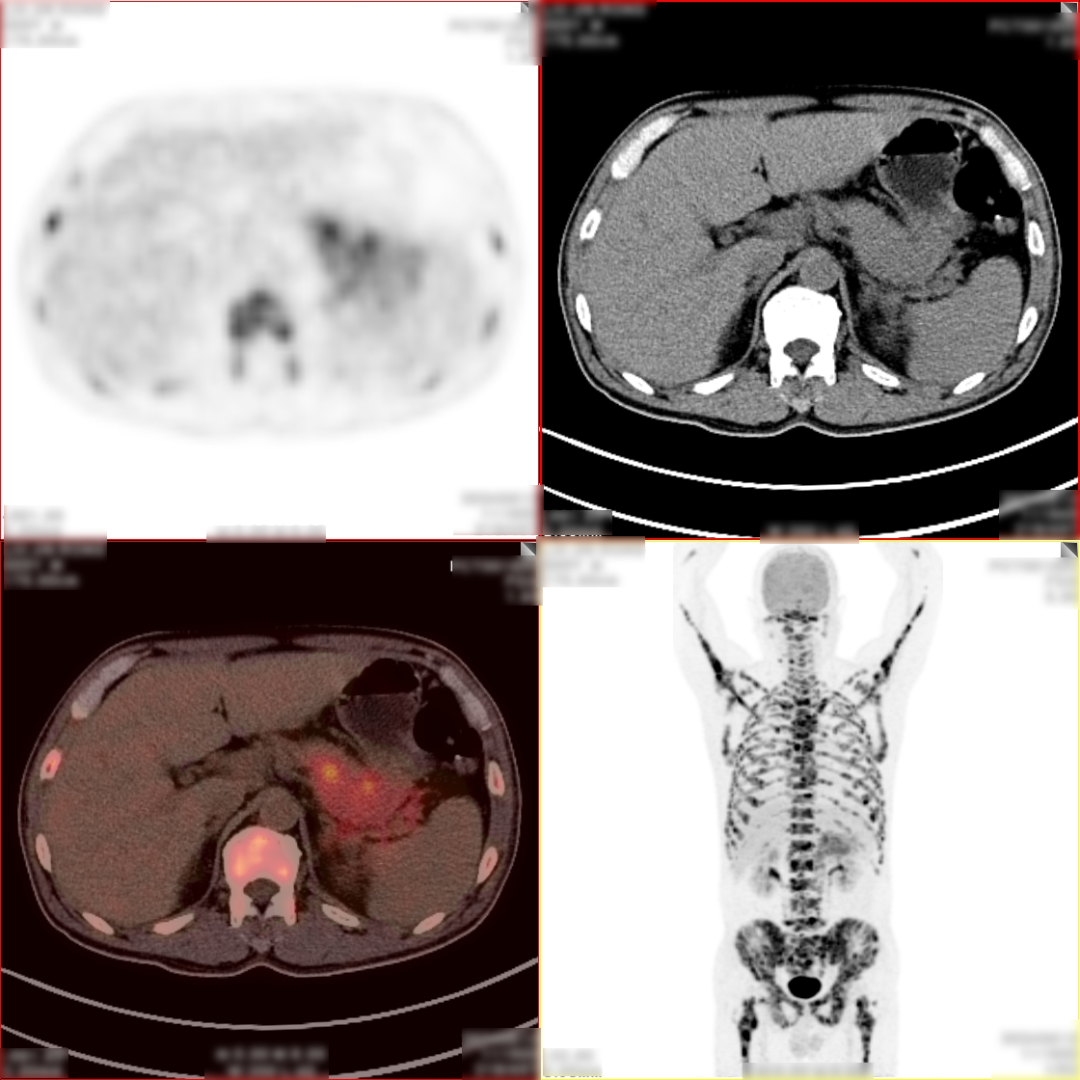

病史:男,55岁,腹痛伴乏力3天入院检查,MR:胰尾部肿物,考虑胰腺癌并多发淋巴结转移;超声胃镜下胰腺活检未见癌细胞,为了解全身状况申请PET检查。

PET/CT检查所见

空腹 6h 以上,静脉注射显像剂 18F-FDG,平静休息 60min 后行全身 PET 及 CT 断 层显像,解剖与功能图像行多层面、多幅显示,影像清晰。

PET/CT诊断意见:

1、胰腺体尾部块状胰腺癌,病灶侵犯相邻胃体部胃壁,并可能侵犯左侧肾周筋膜,肿块远端胰尾部胰管扩张;盆腔少量积液;

2、胰腺尾部周围、中上腹部腹膜后区腹主动脉周围及纵隔内(1R、1L、2R、4R、5、7 组)多发淋巴结转移灶;

3、双侧尺骨近端、双侧肱骨、右侧颞骨、枕骨、蝶骨、双侧下颌骨头、双侧锁骨、双侧肩胛骨、胸骨、脊柱各椎体、双侧各肋骨、骨盆诸组成骨、右侧股骨头、双侧股骨颈及股骨干广泛骨转移灶,其中左侧第 2、4 前肋、右侧第 4、7 侧肋病理性骨折。

PET/CT活检病理:胰腺癌